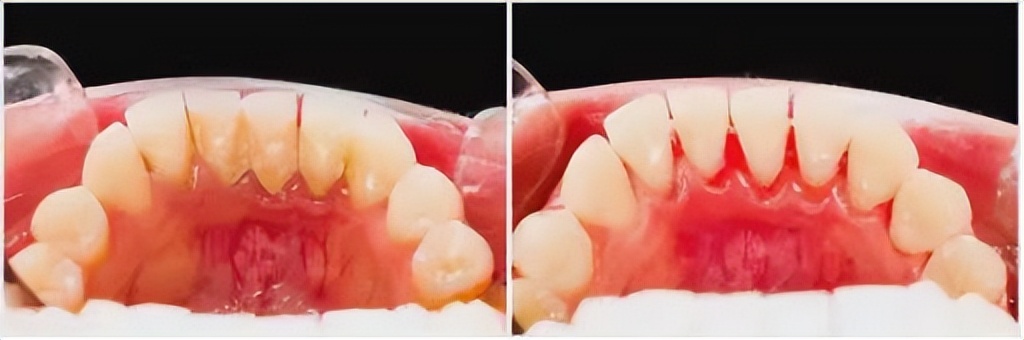

2.定期洗牙是解决口臭的一种非常快速且有效的方式, 洗牙能够将刷牙难以刷掉的牙结石除去,可以有效的避免牙结石、牙斑菌的滋生,及时处理早期的口腔问题,减少口臭的发生。